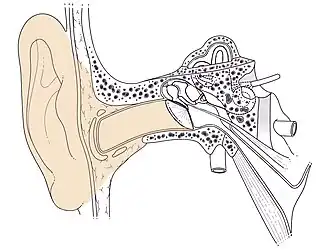

Cet article ne traite que l'anatomie humaine. Le conduit auditif externe, appelé aussi canal auriculaire ou méat acoustique externe, est la partie de l'oreille externe, située entre le pavillon et le tympan.

C'est un canal ostéocartilagineux mesurant de 25 mm de long et de 8 à 10 mm de diamètre, qui dans le plan horizontal présente une double courbure en « S », dans le plan vertical il est ascendant puis descendant à partir de l'isthme du conduit (partie rétrécie médiane). Sa forme générale est celle d'un cylindre aplati d'avant en arrière.

- Une charpente fibrocartilagineuse en dehors, et osseuse en dedans :

- la partie cartilagineuse forme le cartilage du méat acoustique qui fait suite au cartilage de l'auricule. Elle est rattachée à la partie osseuse par une formation fibreuse sur tout son pourtour,

- la partie osseuse est creusée dans l'os temporal et représente la moitié du conduit, soit 14 à 16 mm. Elle est constituée de la gouttière tympanale, qui est soudée à l'écaille temporale.

Conduit auditif externe droit Schéma

Conduit auditif externe droit (Ostéologie)